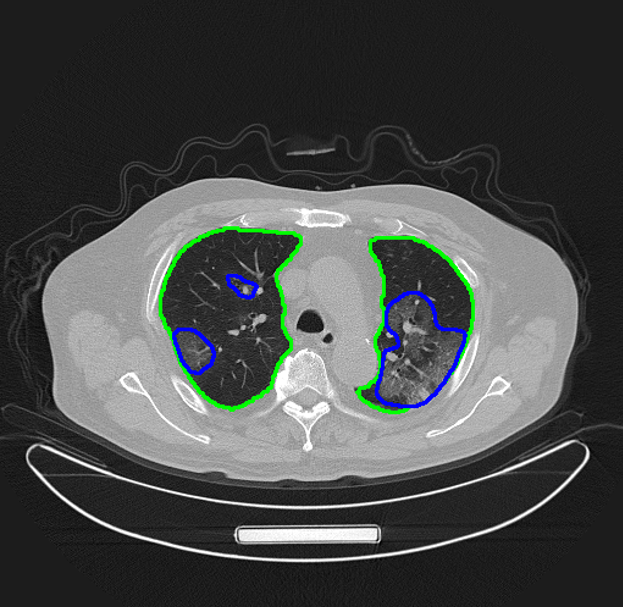

AI对病人肺部和新冠肺炎病灶做了精确的自动分割

“腾讯觅影”对新冠肺炎影像识别模型也做了针对性的优化。通过肺炎病灶区域的精确分割,提供定量分析,以方便影像医生在短时间内对患者病情的严重程度及发展过程做出准确评判。下一步还将提供病例随访等功能,方便医生快速比对患者病情,评估治疗效果。